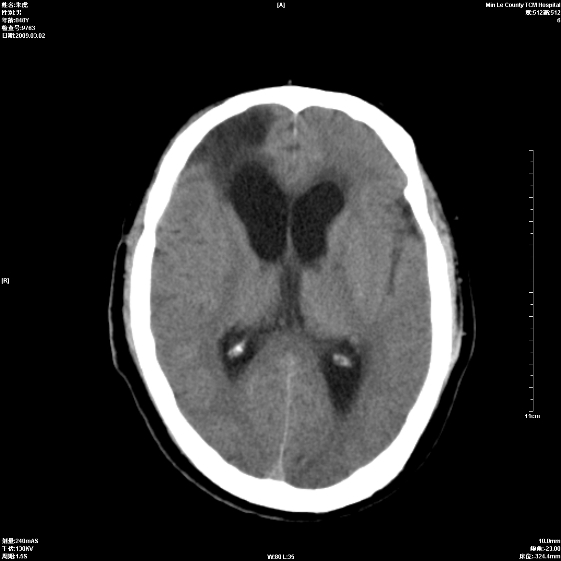

标题: CT18444:男颅咽瘤术后一月复查脑积水增多 [打印本页]

标题: CT18444:男颅咽瘤术后一月复查脑积水增多

梗阻性脑积水。

右额叶软化灶。梗阻性脑积水。

四脑室上方积水,右额叶软化灶。

1)右侧额颞部颅骨术后改变。2)右侧额颞叶脑软化灶。3)脑积水(梗阻性)。

手术后改变1、右额叶脑软化2、梗阻性脑积水。